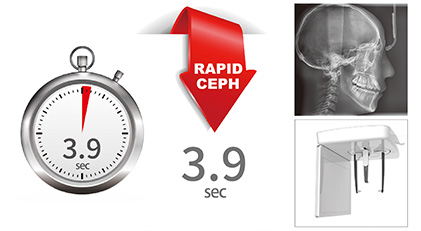

快速头颅侧位拍摄

Smart 12使用更少的扫描时间有效减少运动伪影和加快工作流程。拍摄头颅侧位只需3.9秒,并且在减少辐射剂量的同时提高了影像质量。

| 头颅侧位 | 头颅侧位 | 3.9sec | |